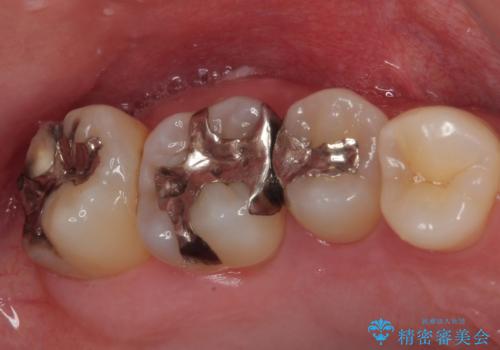

- セラミッククラウン

- 2009~2025年6月

- 000本

- セラミックインレー

最新の症例

Latest cases